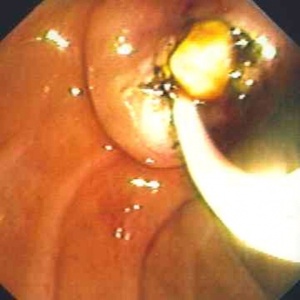

ב- ERCP אפשר להדגים את הכולדוכוס ואת האבן שבתוכו. אם מזהים את האבן, מבצעים פפילוטומיה להרחבת פתח הניקוז. מחדירים סל דרך תעלת האנדוסקופ, לוכדים את האבן ושולפים אותה החוצה. אם האבן גדולה, אפשר לשבור אותה בעזרת הסל ולהוציא את חלקיה (תמונה 3.8).

| תמונה 3.8: הוצאת אבנים דרך הפפילה על-שם ואטר ב-ERCP. | |